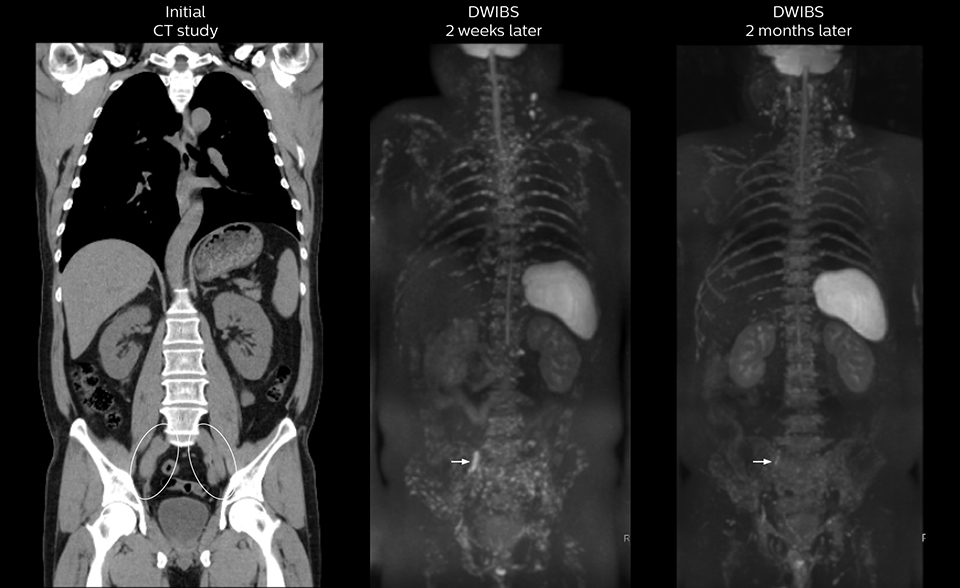

Recognizing the clinical utility of whole body MR imaging, radiologists at Kawasaki Saiwai Hospital (Kasawaki, Japan) began offering whole body diffusion weighted imaging (DWI) in 2009 for oncology patients. In 2012, the hospital installed a Philips scanner, the Ingenia 1.5T. The dStream digital architecture and highly linear gradients of Ingenia allowed them to switch to coronal – rather than axial – whole body DWI, and were key to developing a fast, high quality protocol that has led to increased referrals and decreased dependence on nuclear medicine imaging.

Radiologist Hiroshi Nobusawa, MD, PhD, explains that the coronal DWIBS protocol for whole body DWI is excellent for visualizing lesions in oncology patients. “About 90% of the DWIBS exams are done in this type of patients. The remainder of DWIBS exams are performed to gain information in cases of fevers of unknown origin,” he says.

“The DWIBS sequence’s value in oncology cases is due to the high contrast it creates between lesions and surrounding tissue. Whole body DWI is requested by physicians who need to clarify TNM staging or determine therapeutic strategies, oncologists in need of diagnosis or follow-up scans, surgeons who need to see the presence of distant lesions that are sometimes difficult to detect by CT before surgery, and urologists for the evaluation of bone lesions, and the effect of chemotherapy and radiotherapy.”

“Switching to coronal DWIBS – rather than axial – further shortens scan time,” says Mr. Naka. “Important is that a dS SENSE factor of 5 shortens exam time while high image quality can be maintained, thanks to Ingenia’s dStream architecture.” He adds that the coronal orientation also avoids artifacts that are specific to combining axial images.

“When we use a coronal DWIBS acquisition, we can perform a full whole body examination, including other required sequences, within 30 minutes,” he says.

“This is considerably faster than the previously used exam with axial whole body DWI, which took more than 45 minutes,” he notes. “A shorter exam is more patient-friendly and allows us to also use it on patients in poor health who would have difficulty tolerating a long exam. Limiting the exam time is also helpful for scheduling, because it fits in a normal single exam timeslot.”